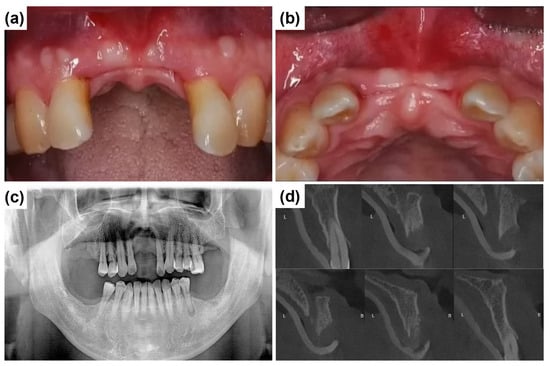

A 58-year-old male patient reported to Mir Dental Hospital at Daegu with missing maxillary central incisors (teeth #11 and #21). The patient was a heavy smoker but had no significant systemic conditions. He revealed that he had lost the teeth three months prior due to periodontal disease. Intraoral examination confirmed the absence of teeth #11 and #21. Figure 2a,b illustrate the clinical presentation at the initial visit, demonstrating severe alveolar ridge resorption and distinct U-shaped gingival recession. Radiographic evaluations, including cone-beam computed tomography (CBCT) and clinical examinations, were conducted to assess bone loss and optimize treatment planning. A panoramic radiograph revealed generalized poor periodontal health (Figure 2c), with notable horizontal alveolar bone loss and vertical bone defects in the edentulous region. Significant labial alveolar bone loss was observed, especially mesially around tooth #22 (Figure 2d).

Figure 2.

Preoperative clinical and radiographic evaluation. (a) Labial intraoral view of the anterior edentulous region (at the initial visit) shows the absence of maxillary central incisors (#11 and #21) and significant alveolar ridge resorption. (b) Occlusal intraoral view of the maxillary anterior ridge, severe horizontal ridge atrophy. (c) Initial panoramic radiograph shows the overall periodontal condition and alveolar bone status. (d) Preoperative intraoral periapical radiograph of the maxillary anterior region illustrates alveolar bone loss and root morphology before implant placement.